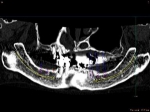

術前レントゲン

術前CT像、下歯槽神経が下あごの中央部を走行しているため利用できる骨の高さが少ない。